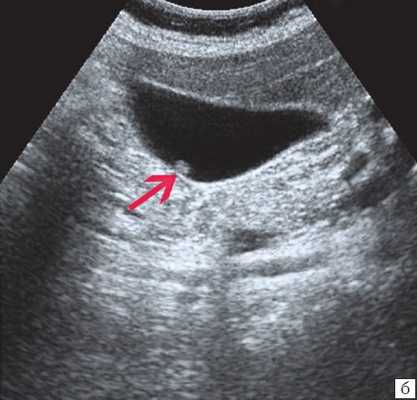

Клиническая картина желчнокаменной болезни многообразна [5-6, 10]. Условно выделяют хроническую болевую, хроническую рецидивирующую, диспептическую, стенокардитическую и ряд других клинических форм. Характерным ультразвуковым признаком конкремента в желчном пузыре является его акустическая тень. Такая тень возникает из-за высокой плотности камня по сравнению с мягкими тканями. Наличие или отсутствие тени помогает отличить камень от полипа желчного пузыря (рис. 4).

![Эхограмма - одиночный конкремент желчного пузыря]()

а) Одиночный конкремент желчного пузыря (подвижная гиперэхогенная структура, дающая четкую теневую дорожку).